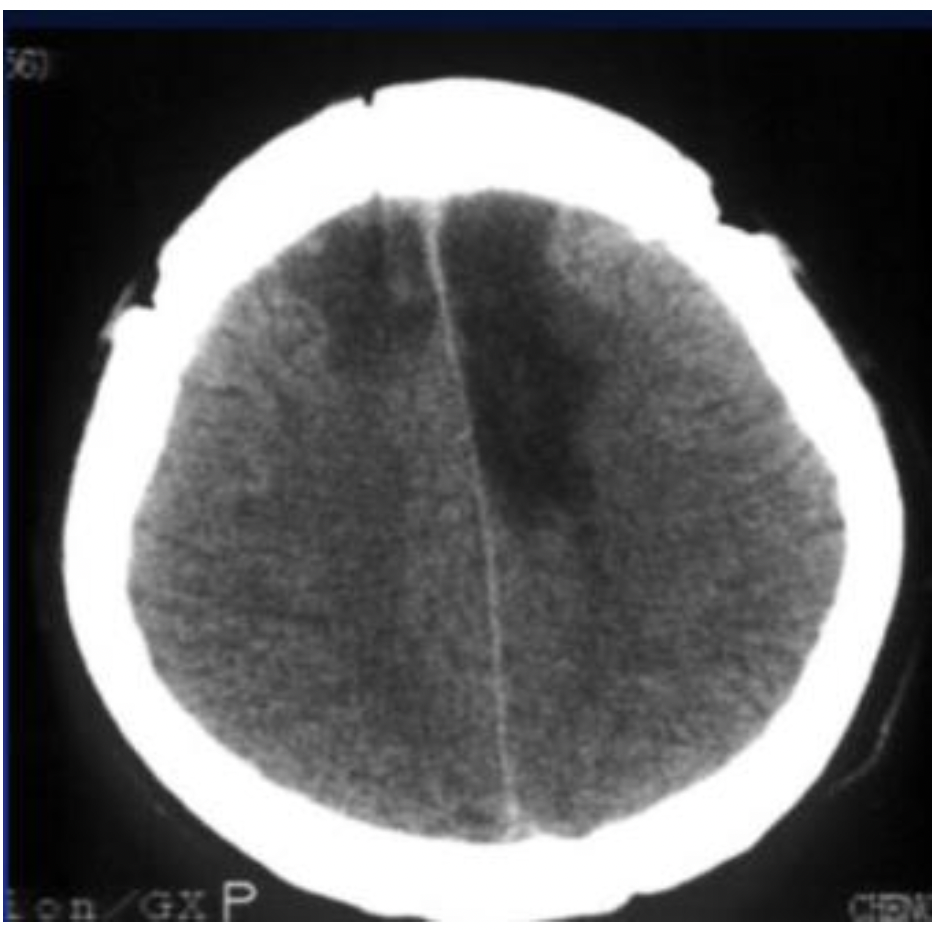

בצילום- החלק ההיפודנסי (כהה) מלמד על שבץ מוחי איסכמה שמתאים לעורק השמאלי.

מה ההבדל בין שבץ איסכמי לשבץ המורגי בהדמיה סמוך לאירוע?

איסכמי- לרוב בשעות הראשונות הסיטי יראה תקין

המורגי- בהדמיה יראו איזור לבן היפרדנסי